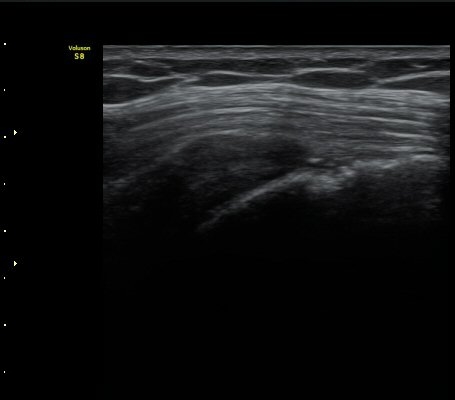

¾î±ú ±Ø»ó°Ç ÃÊÀ½ÆÄ°Ë»ó ±Ø»ó°Ç ºÎÂøºÎ°¡ °üÂûµÇÁö ¾Ê°í ±ÙÀ§ºÎ·Î ´ç°ÜÁ® ÀÖ´Ù(±×¸² 1, 2).

±Ø»ó°Ç Ⱦ´Ü¸é°Ë»ç»ó »ó¿Ï°ñµÎ¸¦ µ¤°í ÀÖ¾î¾ßÇÒ ±Ø»ó°ÇÀÌ º¸ÀÌÁö ¾Ê°í Á¡¾×³¶ÀÌ ÆíÆòÇϰÔ